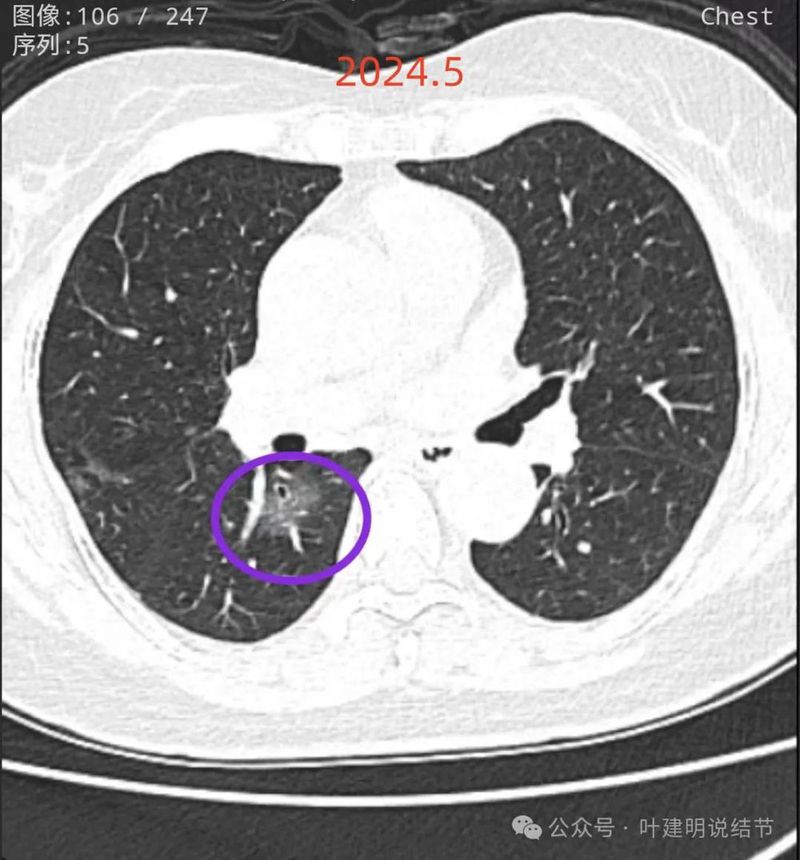

再看2024年5月时的影像:

病灶7:右下叶背段混合密度病灶,灶内血管穿行,支气管壁僵硬,表面不平,轮廓与边界清,较2021年时密度增加不太显著,范围似略有扩大,考虑浸润性腺癌可能性大。

两肺多发磨玻璃结节,部分是混合密度。主病灶是红色这处在左上叶的,对比2021年有明显增大进展,考虑是浸润性腺癌可能性大,或者微浸润性腺癌;粉色的考虑原位癌可能性大;橘色的考虑不典型增生可能性大;黄色的考虑肺泡上皮增生可能性大;紫色的考虑微浸润性腺癌可能性大;绿色的考虑良性的可能性大;蓝色的考虑浸润性腺癌或者微浸润性腺癌;黑色的是2021年的时候比较明显的几处病灶。总体对比来看红色的范围增大比较明显,实性成分也有增加;蓝色的密度增加比较明显。首先考虑是多原发早期肺癌。个人觉得继续随访存在一定风险,当然由于病灶太多,也不是说都靠外科手术能够解决问题的,但是主要的有风险的病灶如果能够手术还是需要手术先解决,其他次要的病灶后续再考虑消融或者其他治疗。我的想法是先做右肺下叶背段切除(紫色,考虑微浸润或浸润)加上叶楔形切除(蓝色),下叶粉色的也可楔切或不切;之后看恢复情况过三个月左右再做左肺上叶切除。其余病灶后续如果随访进展考虑消融控制。意见供参考!为何先建议做右侧:先做右侧是因为右侧切得少,到时候再切左侧的时候,单肺通气更能耐受。如果先做左侧,下次做右侧时,左下叶单肺通气不太能耐受些。而且蓝色这处密度增加明显,又贴着胸膜,它的风险相对来说也较高,或许比左上红色的还高点。所以先做右侧。若非转移,靶向药个人不太建议吃,又不是晚期,是多原发早期肺癌可能性大呀。